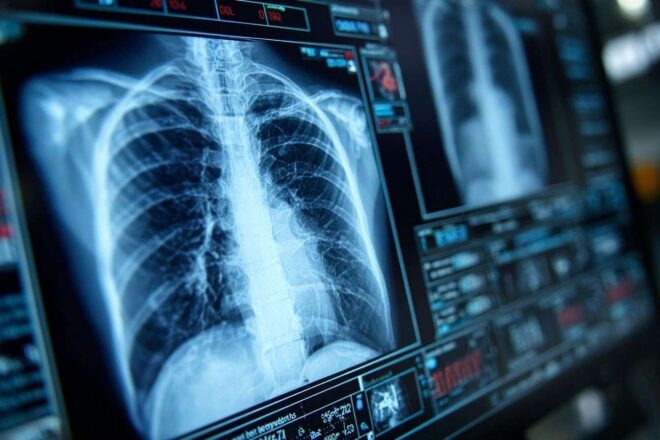

Gros plan d'un scanner thoracique affichant des images complexes sur un écran haute résolution.

Niedrigdosis-CT als Schlüsseltechnologie im Kampf gegen Lungenkrebs